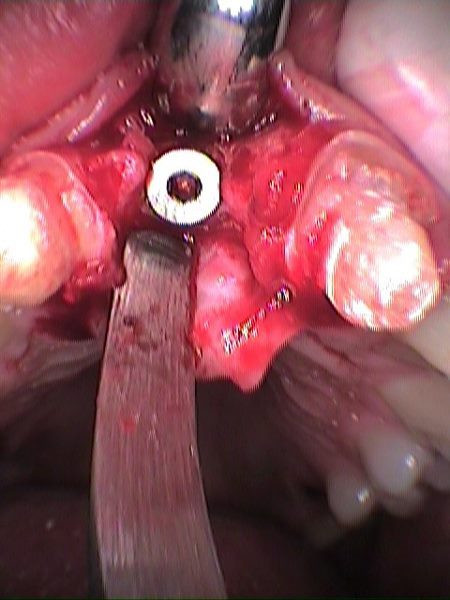

Se remueve tornillo de cicatrización

Implante colocado en incisivo central derecho

Secuencia de colocación de implante